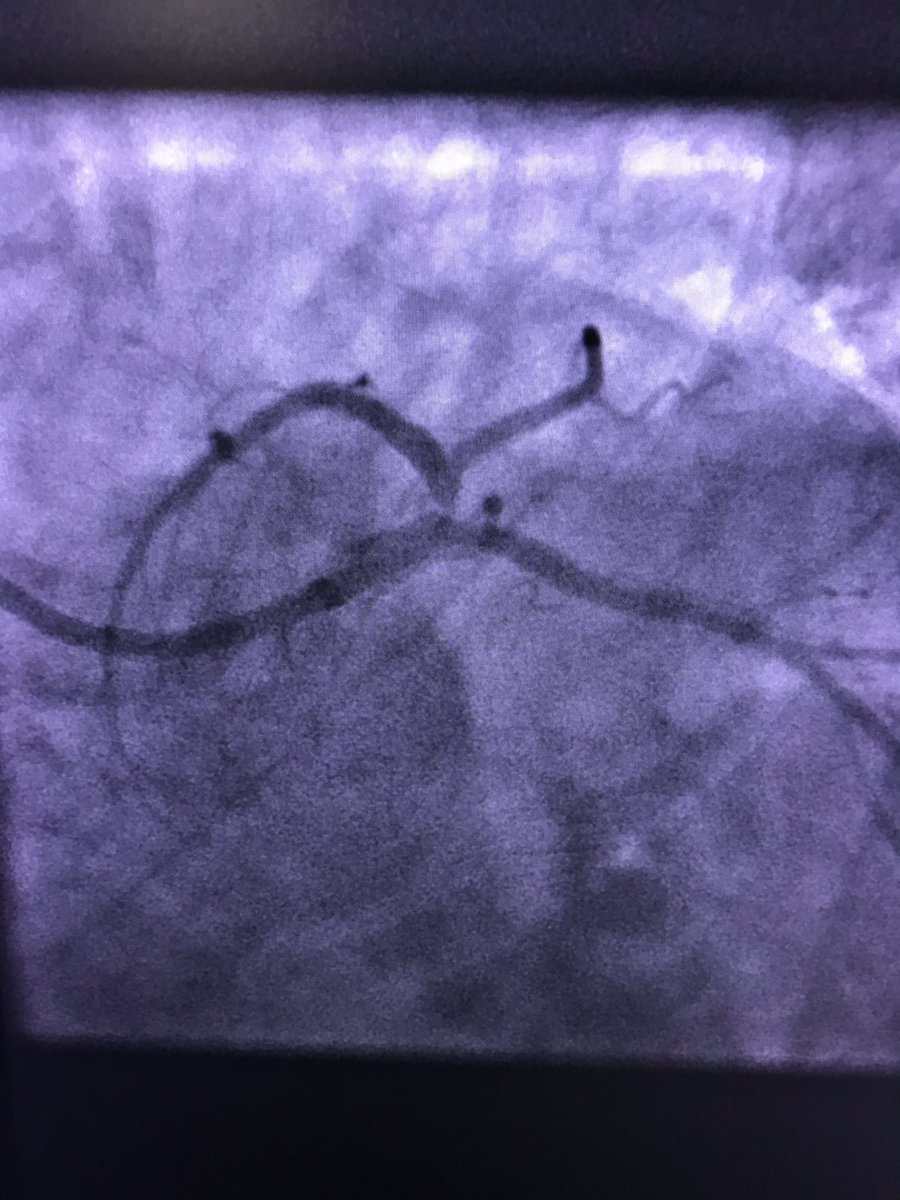

45f #cardiotwitter #safefemoral ,2 hrs symptoms,3am case, #stemi stent into left main from LAD.no#shock ,no#impella. EF40.#alifesaved

istentem's tweet image. 45f #cardiotwitter #safefemoral ,2 hrs symptoms,3am case, #stemi stent into left main from LAD.no#shock ,no#impella. EF40.#alifesaved